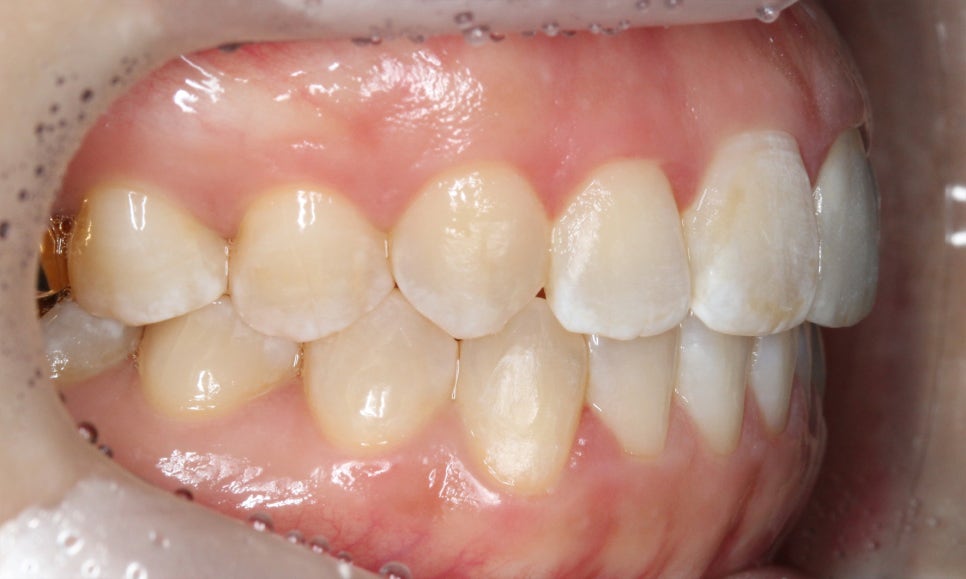

송곳니교정 전 전치부의 overjet 사진을 확인해보면

상악 중절치가 약간 돌출되어 있는 것을 확인할 수 있는데요,

아랫니도 미세하게 crowding이 발견되어 송곳니의

덧니 증상을 해결하면서 전치부 치열을

가지런하게 만들어야 할 것으로 보입니다.